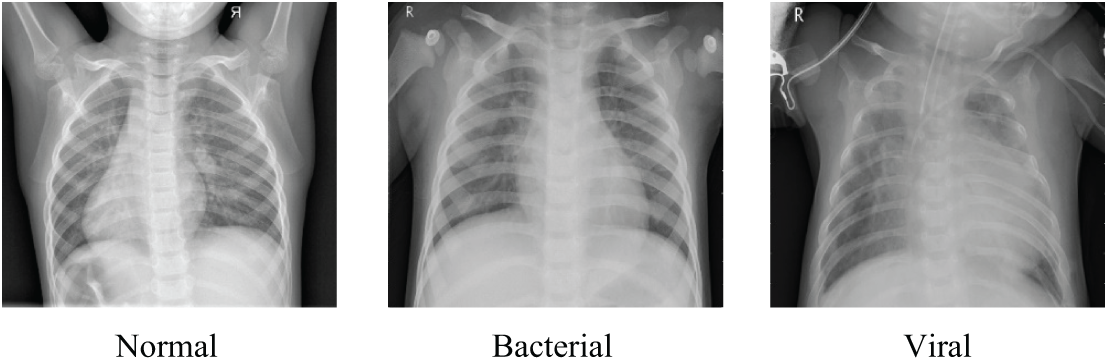

The experimental data were sourced from the publicly available Chest X-ray dataset [11]. The dataset comprised a total of 5856 lung X-ray images, with 1583 normal images and 4273 pneumonia-labeled images. According to the labeling of pneumonia type in the dataset, it can be further subdivided into bacterial pneumonia and viral pneumonia, with the number of images being 2780 and 1493, respectively, and the data distribution are shown in Table 2. The image samples in the dataset are shown in Fig. 7.

Figure 7: Samples from the Chest X-rays dataset

In Fig. 2a, N refers to a normal image, B refers to a bacterial pneumonia image, and V refers to a viral pneumonia image, which serve as training samples for PLW-EfficientNetV2. In Fig. 2b, to increase the diversity of the training samples, PLW-EfficientNetV2 enhances the images by random cropping and horizontal flipping operations, followed by using image normalization techniques so that each pixel in the image is correlated with the global mean and standard deviation, thereby maintaining the global information and non-linear characteristics of the images.